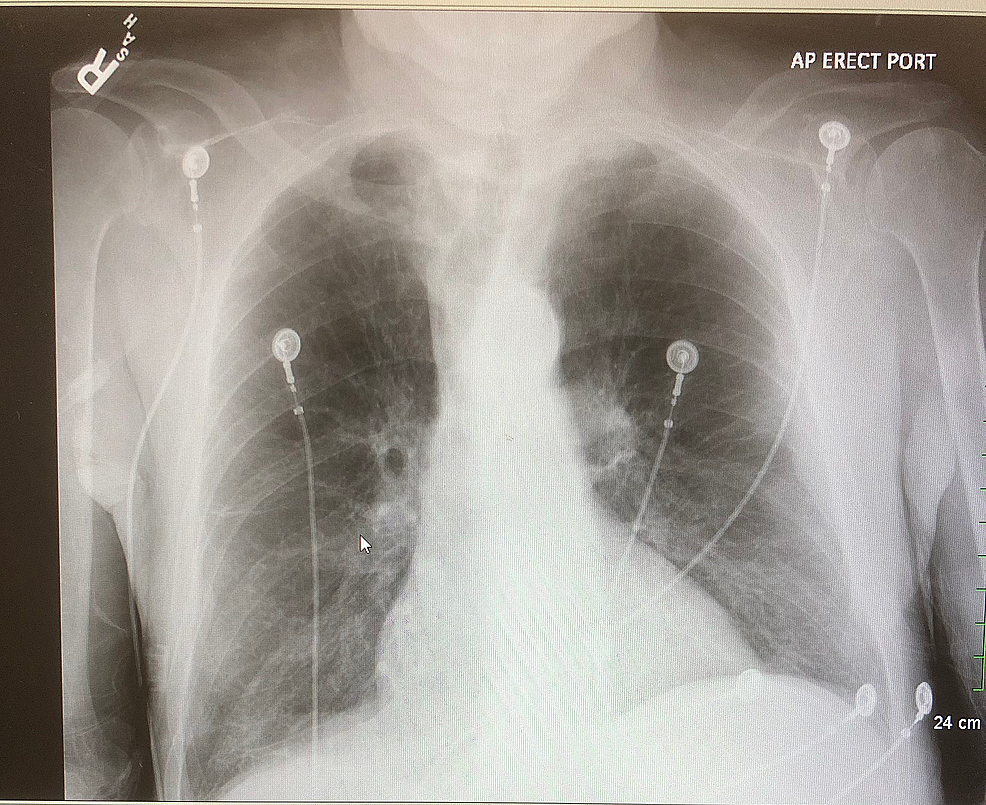

Chest X-Ray Findings In Lupus . As an example, the diagnosis of sle is more likely to be present in a young woman who develops fatigue, arthralgia, and pleuritic chest. In patients showing lung complications, 72% displayed symptoms, which most frequently consisted of pleuritic chest. Systemic lupus erythematosus (sle) is an unusually complex autoimmune disease that is encountered in every radiology subspecialty. Thoracic manifestations of systemic lupus erythematosus. Pleural involvement is common in sle, occurring in up to 93 percent in autopsy series, and can be manifest as pleuritic chest. Please refer to the main article on. Thoracic manifestations of systemic lupus erythematosus (sle) can be variable. On ed presentation the patient’s vital signs showed tachycardia (hr 120s), tachypnea (rr 28), blood pressure (110/60), and an oxygen saturation of 96% on 2l nasal cannula.

Applied Sciences Free FullText Classification and Predictions of Chest X-Ray Findings In Lupus On ed presentation the patient’s vital signs showed tachycardia (hr 120s), tachypnea (rr 28), blood pressure (110/60), and an oxygen saturation of 96% on 2l nasal cannula. Pleural involvement is common in sle, occurring in up to 93 percent in autopsy series, and can be manifest as pleuritic chest. In patients showing lung complications, 72% displayed symptoms, which most frequently. Chest X-Ray Findings In Lupus.

A Case of Seronegative ANA HydralazineInduced Lupus Presenting With Chest X-Ray Findings In Lupus Pleural involvement is common in sle, occurring in up to 93 percent in autopsy series, and can be manifest as pleuritic chest. On ed presentation the patient’s vital signs showed tachycardia (hr 120s), tachypnea (rr 28), blood pressure (110/60), and an oxygen saturation of 96% on 2l nasal cannula. Thoracic manifestations of systemic lupus erythematosus (sle) can be variable. Thoracic. Chest X-Ray Findings In Lupus.